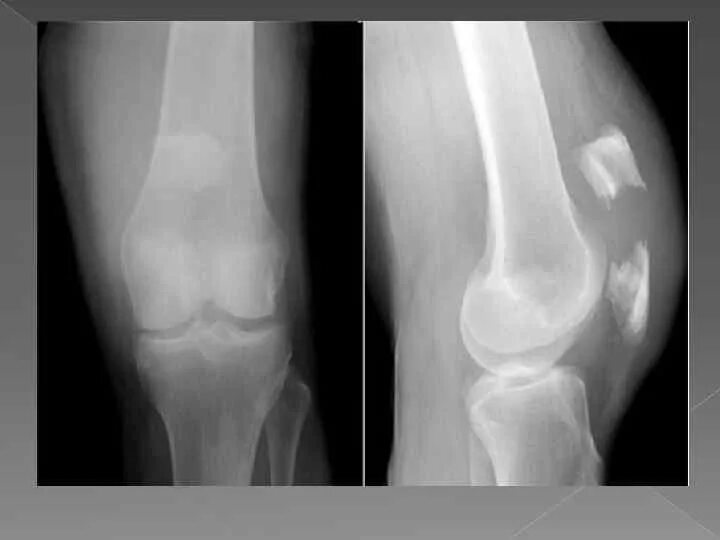

Смещение колена